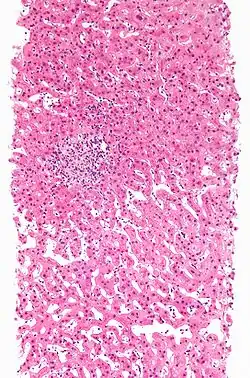

Drug-induced hepatitis with granulomata. Other causes were excluded with extensive investigations. Liver biopsy. H&E stain.

Granuloma

Drug-induced hepatic granulomas are usually associated with granulomas in other tissues and patients typically have features of systemic vasculitis and hypersensitivity. More than 50 drugs have been implicated.

Causes:

Allopurinol, phenytoin, isoniazid, quinine, penicillin, quinidine